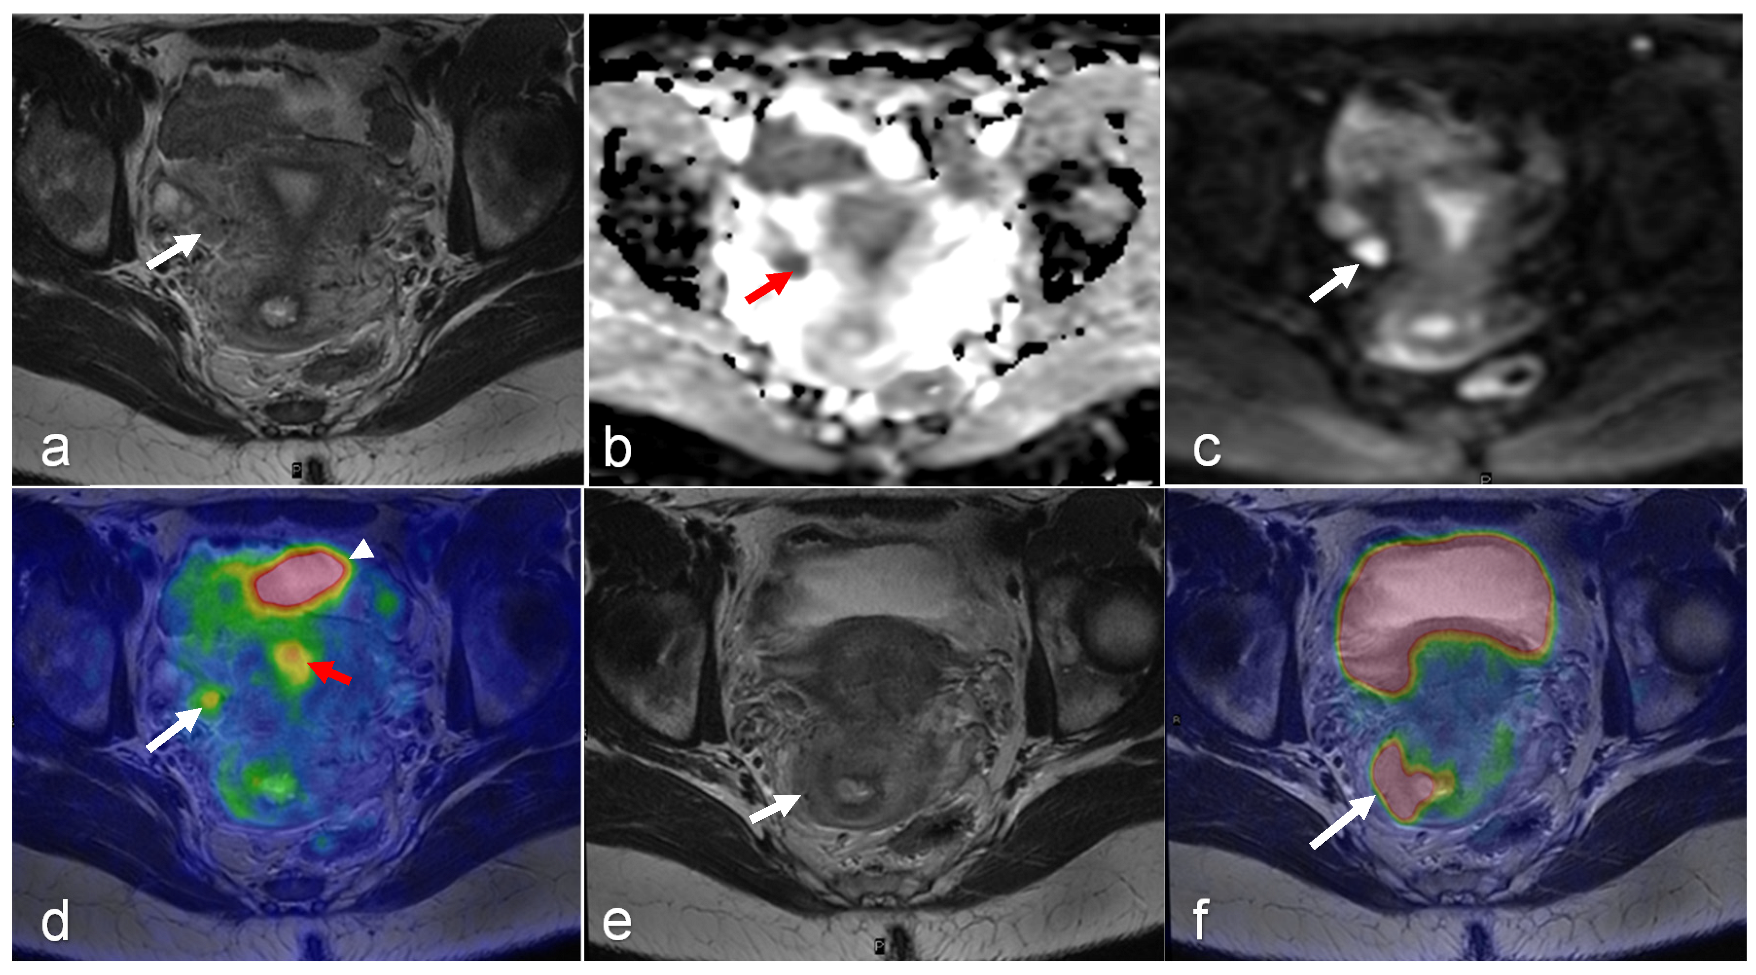

- Xi, Y.; Sun, L.; Che, X.; Huang, X.; Liu, H.; Wang, Q.; Meng, H.; Miao, Y.; Qu, Q.; Hai, W.; et al. A comparative study of [(68)Ga]Ga-FAPI-04 PET/MR and [18F]FDG PET/CT in the diagnostic accuracy and resectability prediction of ovarian cancer. Eur. J. Nucl. Med. Mol. Imaging 2023, 50, 2885–2898. [Google Scholar] [CrossRef]

- Fiaschetti, V.; Calabria, F.; Crusco, S.; Meschini, A.; Nucera, F.; Schillaci, O.; Simonetti, G. MR-PET fusion imaging in evaluating adnexal lesions: A preliminary study. Radiol. Med. 2011, 116, 1288–1302. [Google Scholar] [CrossRef] [PubMed]

| Ovarian | Benefit(s) | Evaluates for metastatic disease and possible lymph node involvement. Useful for determining response to chemotherapy, can predict diaphragm and omental involvement [32] | Outperforms CT and PET/CT for detecting ovarian cancer [33] Helps differentiate between benign, malignant, and borderline masses by DCE-MRI and DWI [34] Useful for treatment planning in advanced ovarian cancer [32] | Evaluating possible metastatic extraperitoneal spread of the disease and metastatic lymph nodes [32] Detects recurrent disease [32] predicts treatment response after NAC [35,36,37,38,39,40] | Hybrid molecular and anatomic imaging provides high soft tissue contrast with lower radiation dose Detects lymph node metastases with high accuracy [32] |

| Pitfall(s) | Limited soft tissue evaluation and differentiation. Limited in evaluating local extent of disease | Limited sensitivity in detecting small peritoneal implants [41] | Lack of reliable differentiation between borderline and benign tumors according to ESGO/ISUOG/IOTA/ESGE Consensus Statement on pre-operative diagnosis of ovarian tumors. No clear cut-off value for maximum standardized uptake value for differentiation between benign and malignant ovarian tumors [32] Not recommended for primary detection of ovarian cancer [32] The physiologic FDG uptake in pre-menopausal ovaries can be mistaken with malignancy [25,26,27] | Less sensitive for detection of pulmonary nodules compared with PET/CT | |